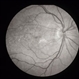

By Michael P. Kelly, FOPS

Duke University Hospital - Uploaded on Sep 14, 2012.

- age-related macular degeneration (AMD)

- Michael P. Kelly, FOPS Director, Duke Eye Center Labs, Duke Universtiy Hospital

Fundus camera

Zeiss FF450